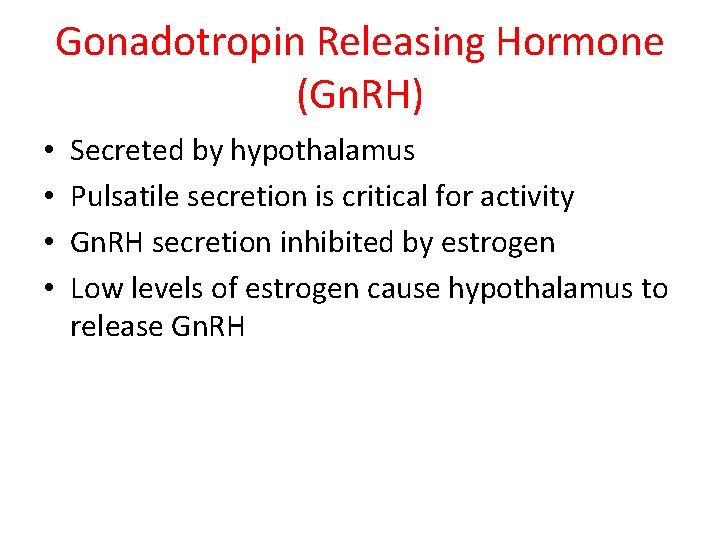

Gonadotropin Releasing Hormone (Gn. RH) • • Secreted by hypothalamus Pulsatile secretion is critical for activity Gn. RH secretion inhibited by estrogen Low levels of estrogen cause hypothalamus to release Gn. RH